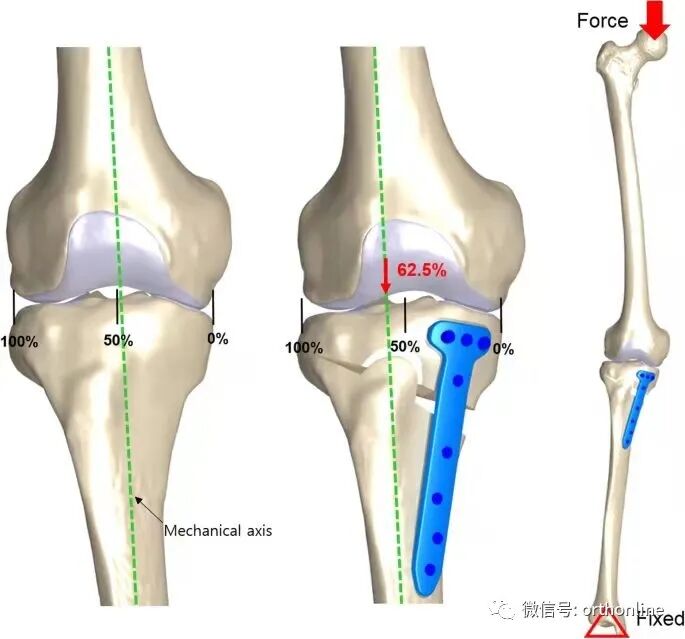

3.1 TCVO

图3

传统的HTO技术无法对关节内畸形进行矫正,因此在合并外侧半脱位的重度膝关节骨关节炎病例中往往难以达到满意的治疗效果。Chiba[9]基于传统HTO技术所面临的困境,于1992年提出了胫骨髁外翻截骨术(tibial condylar valgus osteotomy, TCVO)。TCVO为开放性楔形HTO的一种,由胫骨近端内侧向髁间隆起行"L"形截骨,旨在矫正膝内翻、外移下肢力线的同时修复半脱位的外侧膝关节。日本学者Teramoto T[10]等认为TCVO适用于所有年龄、所有等级的膝内翻OA患者。TCVO的基本原则是通过关节内畸形的关节内矫正来稳定膝关节。这种关节内截骨术改善了骨性和软组织的不稳定性,不需要单独的韧带重建。临床结果证实经tvo治疗后,患者疼痛得到改善,能够恢复繁重的体力劳动和运动活动。国内学者王峰、康庆林团队[11]对接受TCVO手术的内翻型单间室膝关节骨关节炎患者32例(45膝)进行回顾性分析,发现TCVO治疗膝关节外侧间隙增宽、关节线会聚角增大的内翻型单间室膝关节骨关节炎可以取得良好的早期疗效,有效矫正膝关节内翻畸形并外移下肢机械力线,缓解术后早期膝关节疼痛及改善日常活动能力。